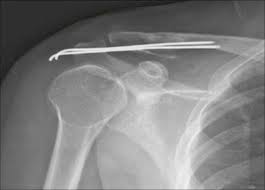

الأشعة السينية

الطريقة الأساسية للتحقق من وجود كسر الترقوة هو عن طريق الأشعة السينية من الترقوة من أجل تحديد نوع الكسر ومدى الإصابة في معظم الحالات، سيتم اتخاذ الأشعة السينية كلا من عظام الترقوة لأغراض المقارنة.

تحدد الأشعة السينية مدى كسر الترقوة، وتحديد موقعها وتحديد ما إذا كان هناك إصابة في المفاصل.

العلاج الجراحي

- أو مسامير

- أو قضبان